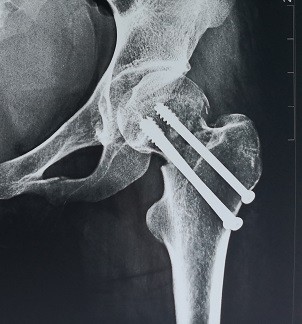

游离腓骨治疗股骨颈不愈合